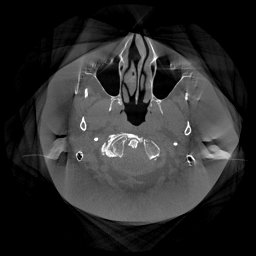

The results for simulated noisy data are shown in Fig. 2. The first and third rows display two representative slices from the test set, and the second and fourth rows present the corresponding error maps. The traditional WCE method suppresses cupping artifacts and recovers some missing anatomical structures but still shows noticeable deviations from the ground truth. Predictions from the four diffusion-based models demonstrate a markedly improved ability to restore anatomical structures. Among them, cDDPM fails to fully reconstruct the patient bed and retains residual noise in its outputs. This noise is attributable to an incomplete reverse denoising process rather than residual Poisson noise, as evidenced in our noise-free experiments (Fig. 5 in the Appendix). PatchDiffusion, diffusionGAN, and I2SB achieve similar visual quality, with I2SB producing the cleanest and most consistent reconstructions.

Quantitative results in Tab. V further confirm I2SB’s superiority over conventional deep learning methods such as FBPConvNet and Pix2pixGAN across RMSE, PSNR, and SSIM. Compared to other diffusion models—including cDDPM, PatchDiffusion, and cLDM—I2SB delivers higher image quality, while diffusionGAN achieves comparable quantitative performance. However, I2SB demonstrates a significant advantage in inference efficiency, as summarized in Tab. IV.

III-D Real Clinical Data Experiment

The experimental results on clinical head data are shown in Fig. 4. The reference images were reconstructed using the fast iterative shrinkage-thresholding algorithm (FISTA) with total variation regularization from non-truncated projection data. In the WCE reconstructions (Fig. 4(b)), severe truncation prevents accurate recovery of anatomical structures outside the FOV. Despite being trained solely on simulated data with a domain gap, all deep learning models can restore a substantial portion of the missing anatomy. Among them, the diffusion-based methods recover soft-tissue boundaries more faithfully than the conventional deep learning approach FBPConvNet, highlighting their stronger image generation capability. However, cDDPM reconstructions exhibit more noticeable noise than those from other methods, consistent with the simulated data results. The patchDiffusion model introduces artifacts within the FOV, likely due to its patch-wise processing strategy. While I2SB shares the same limitations as other diffusion models in perfectly restoring soft-tissue detail, it produces fewer residual noise patterns and fewer artifacts within the FOV boundaries. Overall, Fig. 4 demonstrates the strong efficacy of I2SB in reconstructing real CBCT data.